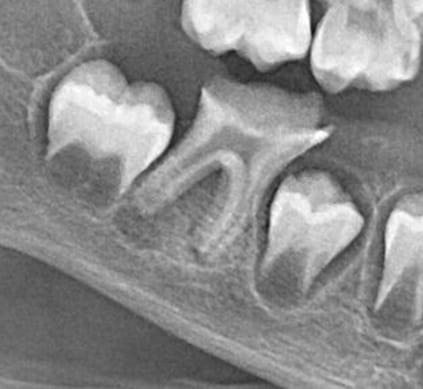

Детальніше...У Центрі Дитячої Стоматології лікаря Ковнацького ми віримо, що візит до стоматолога має бути для дитини не приводом для страху, а кроком до здорової та щасливої посмішки. Наша філософія базується на глибокому розумінні дитячої психології та фізіології, адже дитячі зуби потребують особливого підходу, а малюки – щирої турботи та довіри.